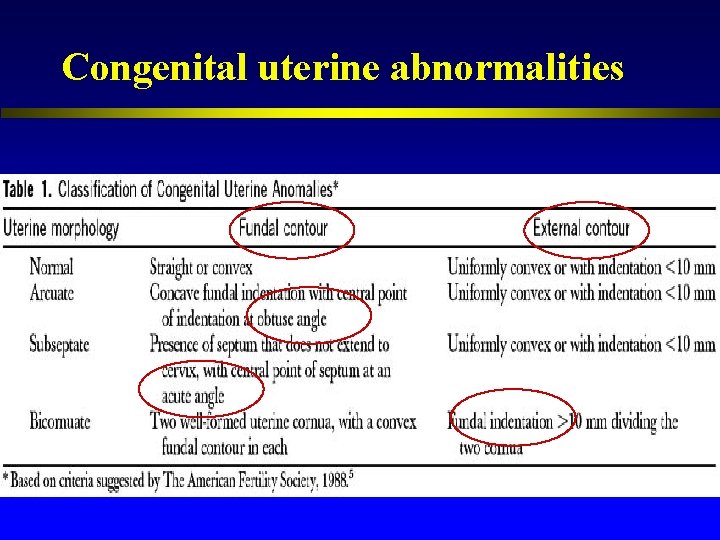

Congenital uterine abnormalities ASRM classification

Congenital uterine abnormalities